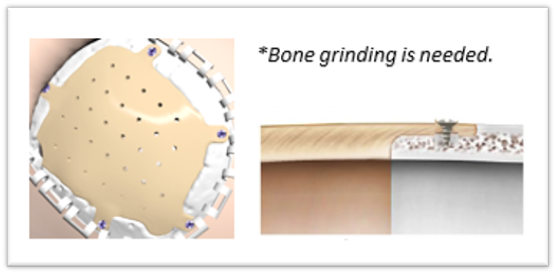

Puente Plano

Indicado en regiones frontales y temporales.